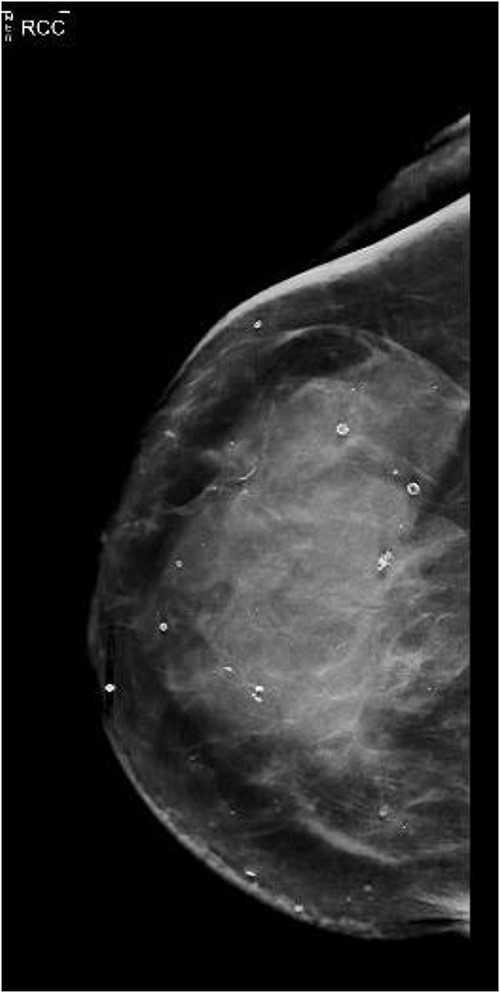

She presented again in 2019 after a fall when she had also complained of bruising in her right breast. The patient had also complained of occasional nausea and abdominal cramping for the past few weeks. A bilateral mammogram was performed on 22 March 2019, which showed dense skin thickening along with medial inferior asymmetry (Fig. 1). US breast was obtained, and a core needle biopsy was done, which showed invasive lobular carcinoma, T3N1M1, estrogen receptor (ER) positive, progesterone receptor (PR) negative, HER2neu negative.

CT abdomen/pelvis displaying gastric wall thickening, coronal view.